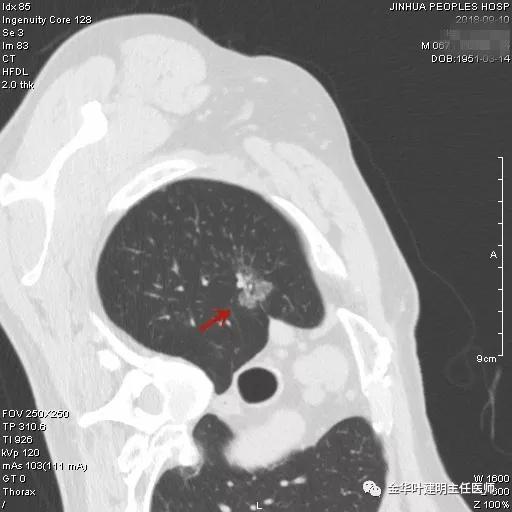

金华的阚某,今年67岁,前些日子因为“咳嗽、咳痰”到金华市人民医院就诊,因为考虑肺部感染,建议其住院抗炎治疗及进一步完善胸部CT等检查,结果示:右肺上叶磨玻璃结节,建议靶扫描及病理学检查;两肺多发感染性病变;左下支气管扩张等诸多肺部疾患。其CT检查影像如下:

上图示右中叶及左下叶感染灶